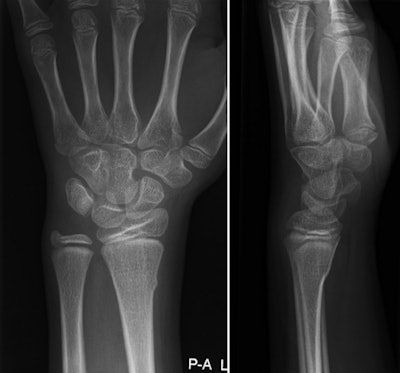

Buckle fracture of the distal radius in a 9-year-old girl. Left, posteroanterior view; right, lateral view. Images courtesy of Dr. Annelie Slaar.The six-variable clinical model had a specificity of 95.9% for detecting distal forearm fractures. In 2009, 8,930 per 100,000 children presented with a wrist injury; using the protocol would have reduced the number of requested x-rays by almost 2,000 per 100,000, or 22%, the authors wrote. The protocol also could have reduced healthcare costs by 96,000 euros ($108,830 U.S.) per 100,000 children annually.